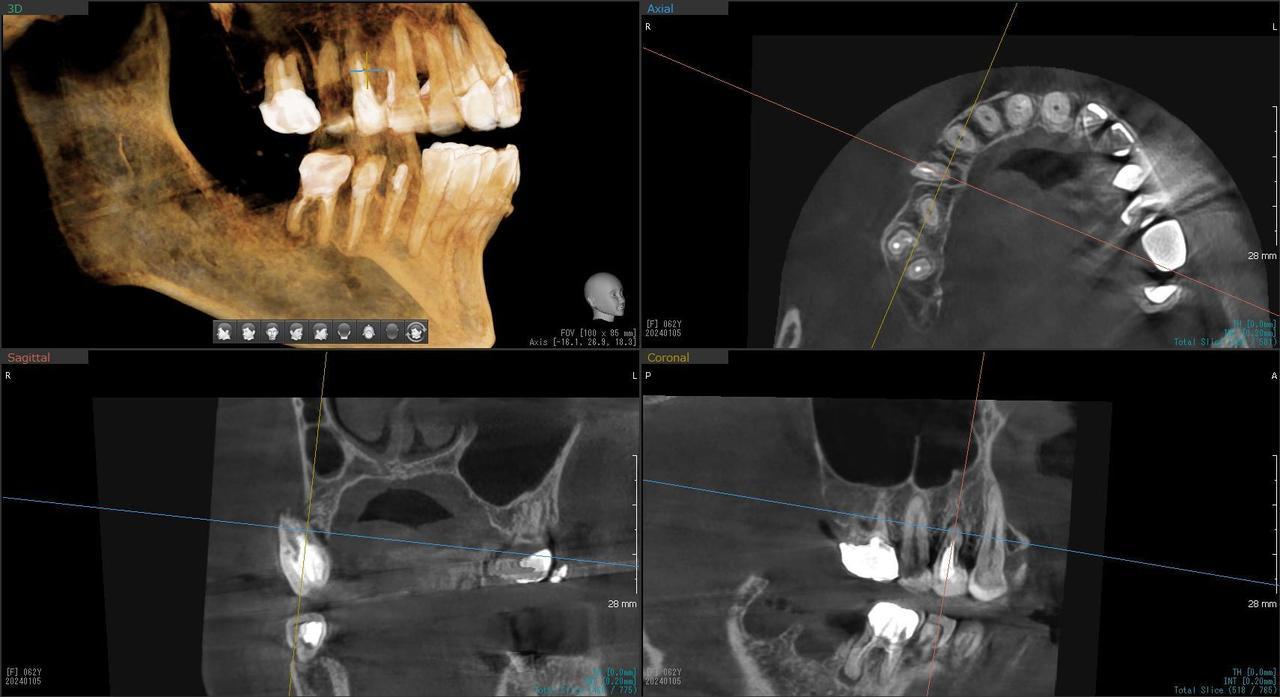

5.右上6番の歯根が破折したに大きな骨欠損を生じたケースに対して、通常なら、大幅な増骨手術(GBRとサイナスリフト)が必要で、最低1年は、かかるケースを、骨補填材なしで、インプラント埋入後、2.5か月で治療を終えたケース

Before

枚方市のインプラントの症例

H・M様 女性 60代

症状としては、左上6番の歯根が歯根が破折したために、炎症が起き、上顎洞底までの及ぶ大きな骨欠損がおきていた、

治療法としては、動揺がひどくなってきて、炎症の症状もあったため、抜歯を希望。抜歯後にインプラント治療を希望したために、CTを撮影したところ、かなりの骨欠損が生じていた。インプラントは不可能か大幅な増骨手術が必要なるようなケースであったが、ご自分の骨が少し残っていた部分にエクストラワイドインプラントで固定をとることと、グラフトレスサイナスリフトを併用する計画を立て、インプラント埋入術を施行。2か月後、インプラントがデータ測定上安定したために、光学印象で印象を行い、2か月半後に上部としてジルコニアクラウンを装着して治療を終えています。

治療結果として、大幅な骨欠損があったが、2か月半という短時間で治療を終えることができた。通常のサイナスリフト等の大幅な増骨手術を行った場合、患者様に、肉体的、金銭的、時間的な負担をかけることになったが、グラフトレスサイナスリフトとエクストラワイドインプラントを使用することにより、そのことを避けることができた。

治療の期間・回数:治療回数インプラント埋入後6回

治療の価格:363000円(税込)

治療費の内訳:インプラント基本料(フィックスチャー(メガジェンインプラントANYONE) 及び手術費用、投薬費用、レントゲン費用、インプラント上部費用(アバットメントおよびジルコニアクラウンの費用用)330000円(税込み)左上6グラフトレスサイナスリフト費用 33000円(税込)